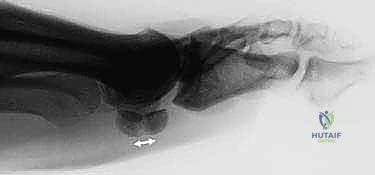

2. التصوير الإشعاعي (X-Rays)

الأشعة السينية هي الخطوة الأولى في التصوير. يتطلب الأمر زوايا تصوير خاصة (Axial Sesamoid View) لرؤية العظام السمسمية بوضوح دون تداخل مع عظام المشطية.

* تحدي تشخيصي: حوالي 10% إلى 30% من الناس لديهم عظمة سمسمية مقسمة خلقياً (Bipartite Sesamoid)، والتي تبدو في الأشعة وكأنها مكسورة. يميز الدكتور هطيف بين الكسر الحقيقي والتقسيم الخلقي من خلال فحص حواف العظمة (حواف الكسر تكون حادة وغير منتظمة، بينما حواف التقسيم الخلقي تكون ناعمة ومستديرة) ومقارنتها بالقدم السليمة.

4. التصوير المقطعي المحوسب (CT Scan)

في الحالات المعقدة التي يخطط فيها الدكتور للتدخل الجراحي، يوفر التصوير المقطعي صوراً ثلاثية الأبعاد تفصل حجم الكسر، وعدد الشظايا العظمية، ومدى تباعدها، مما يساعد في وضع خطة التثبيت الداخلي بمنتهى الدقة.